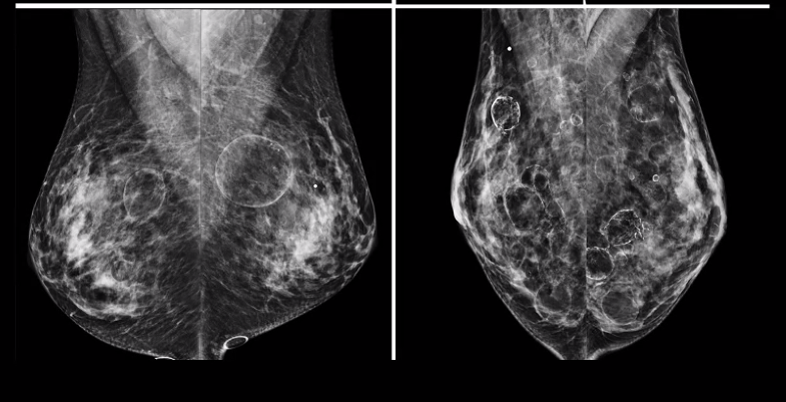

Dermatomyositis

autologous fat injection

deep oil cysts bilaterally - a lot of them

what bir-rads?

BR-2. multiple popcorn (dystrophic) calcs = multiple degenerating fibroadenomas